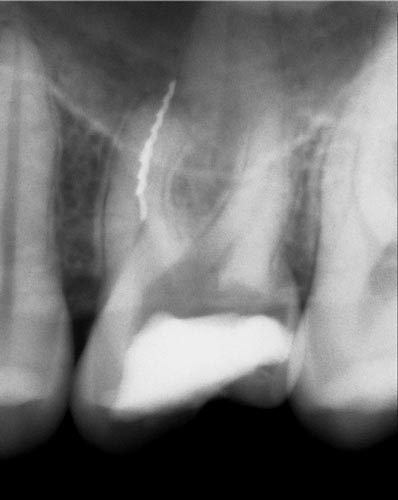

Проблематика сепарованих  файлів

Погляд на сепаровані інструменти. Статистика поломок. Вплив на успішність ендодонтичного лікування. Протокол ухвалення рішення про вилучення уламка. Процедура вилучення за допомогою ультразвуку та альтернативні методики (Ендо ковбой, Петля Тераучі, система Кантервіль, ІРС.). Супутні ускладнення під час вилучення уламків. Мініінвазивна техніка вилучення.

• Вплив на прогноз.

• Ухвалення рішення про необхідність вилучення.

• Відсоток успішності в залежності від рівня поломки, за що не треба братися однозначно.